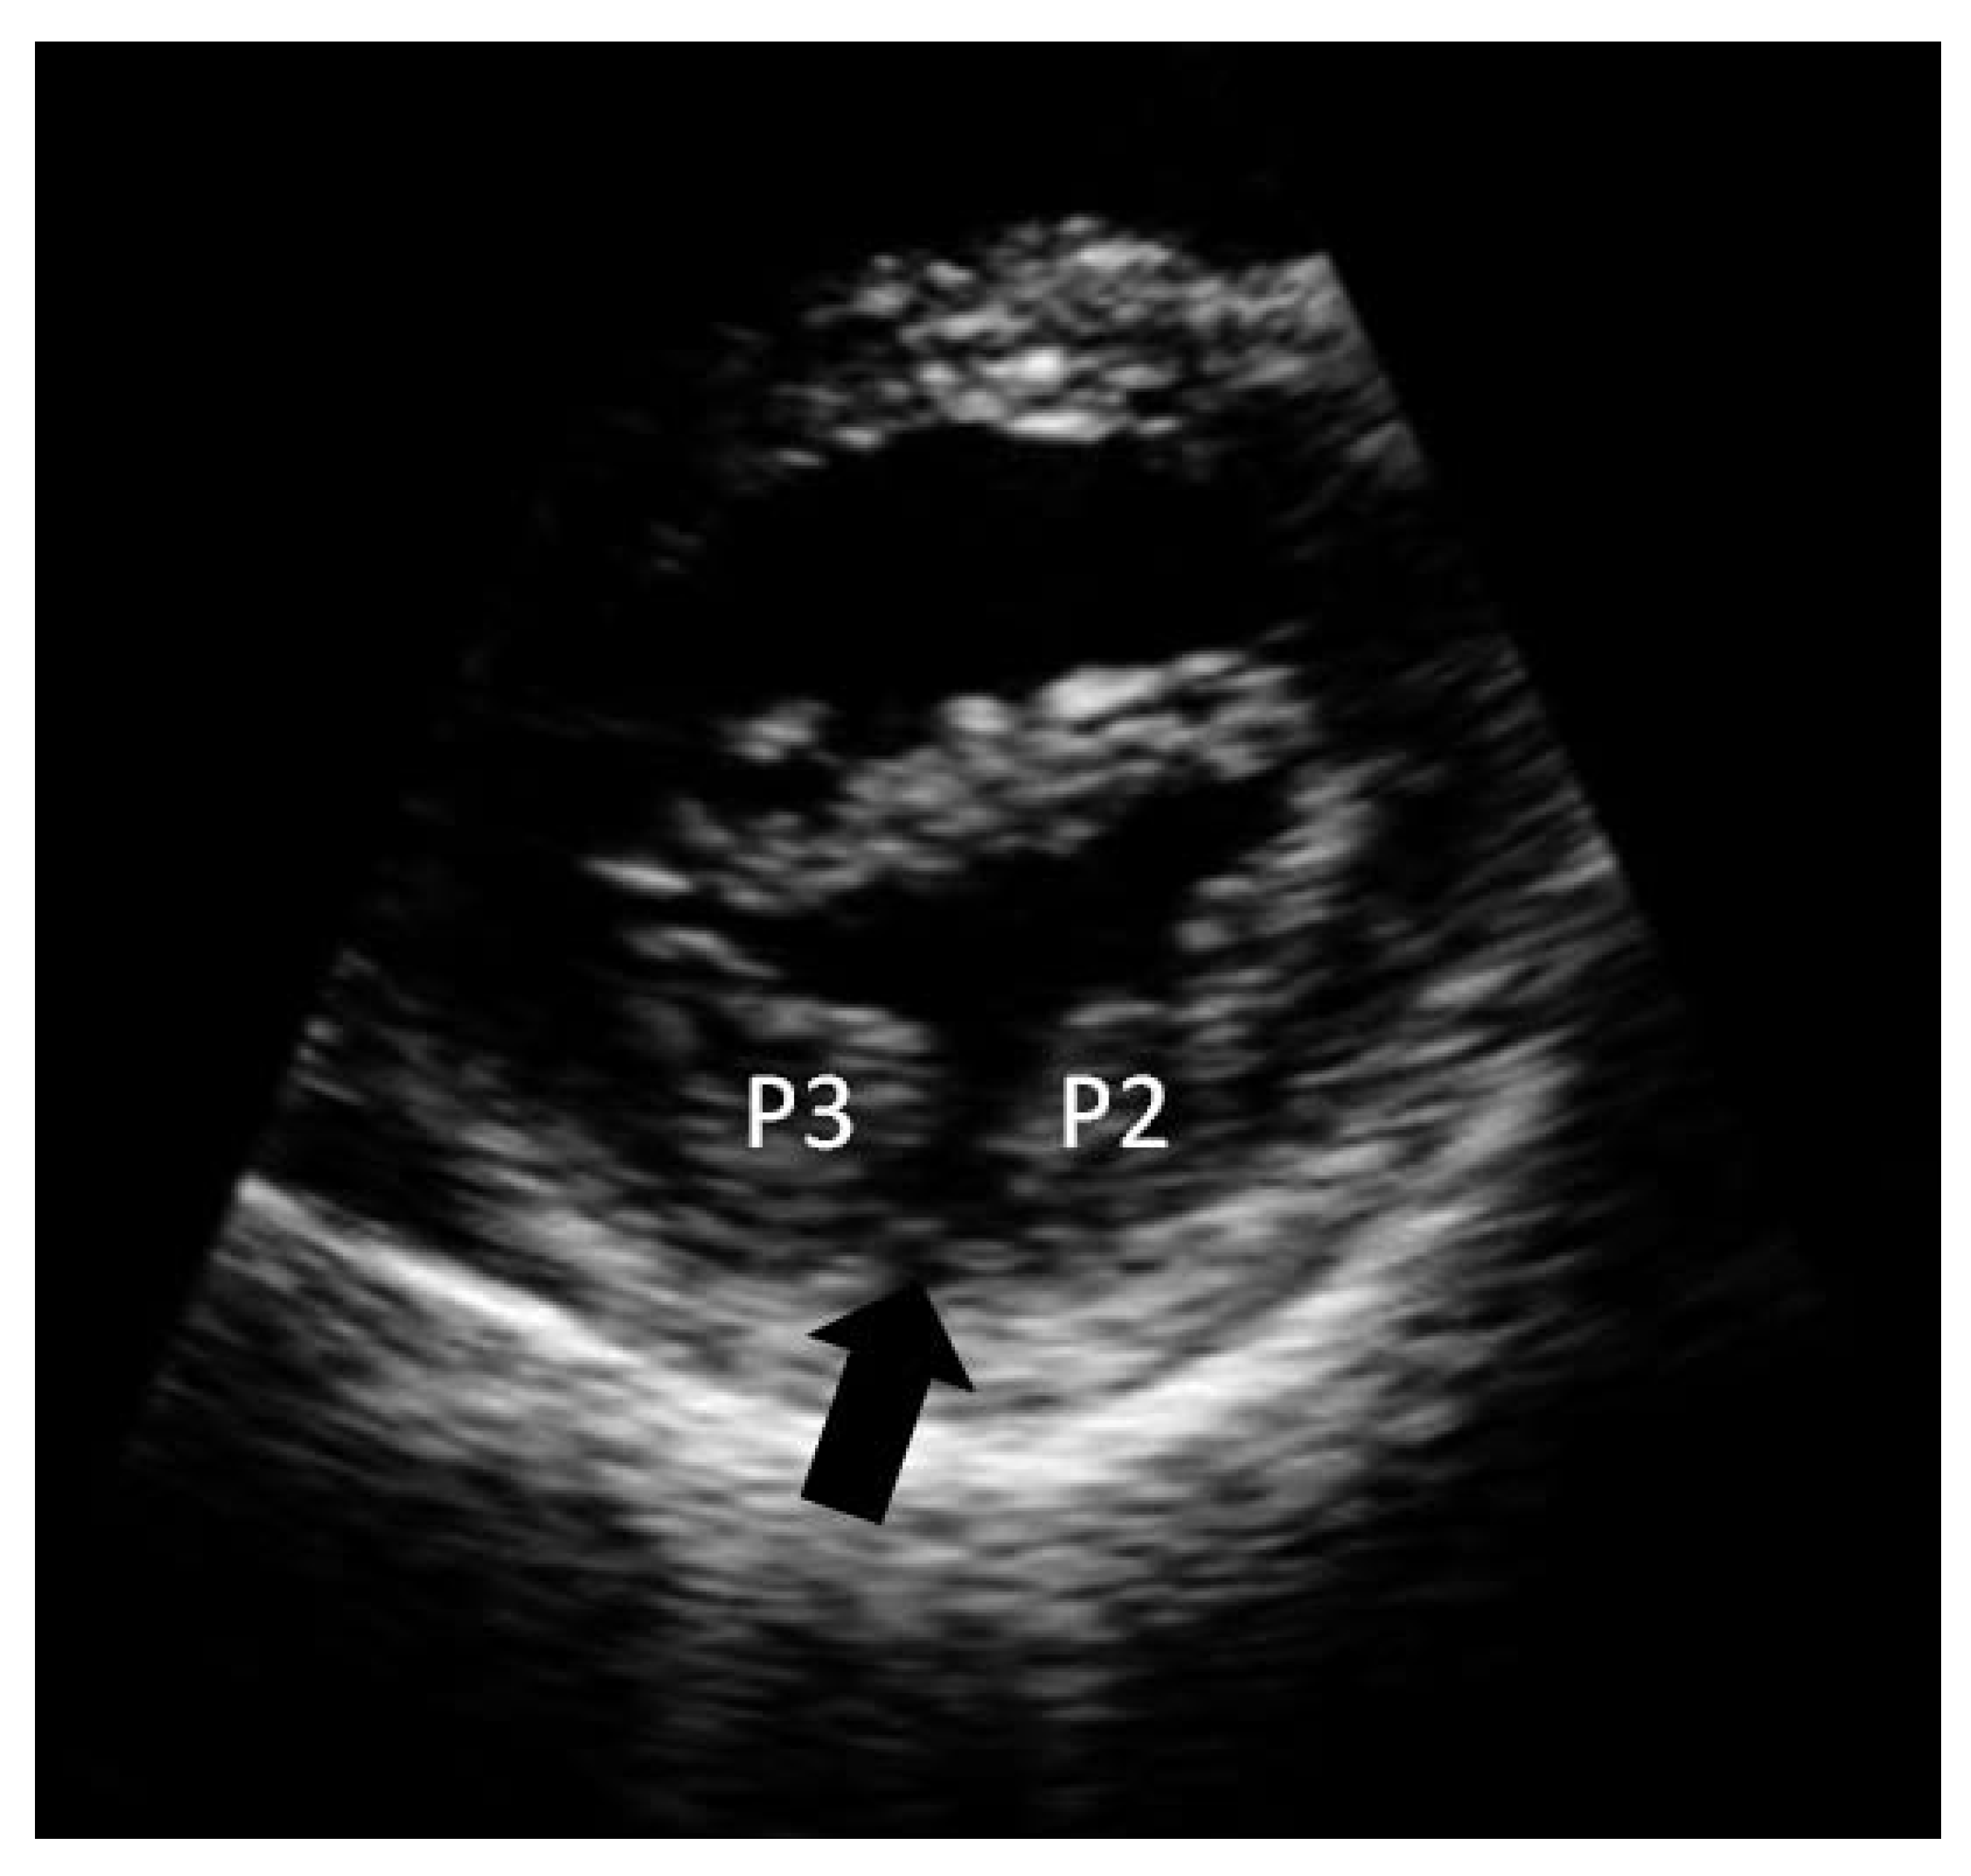

Isolated Posterior Mitral Valve Cleft

Case Report